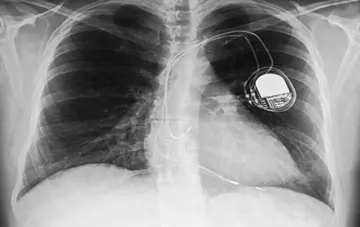

قلب - صفحه 3